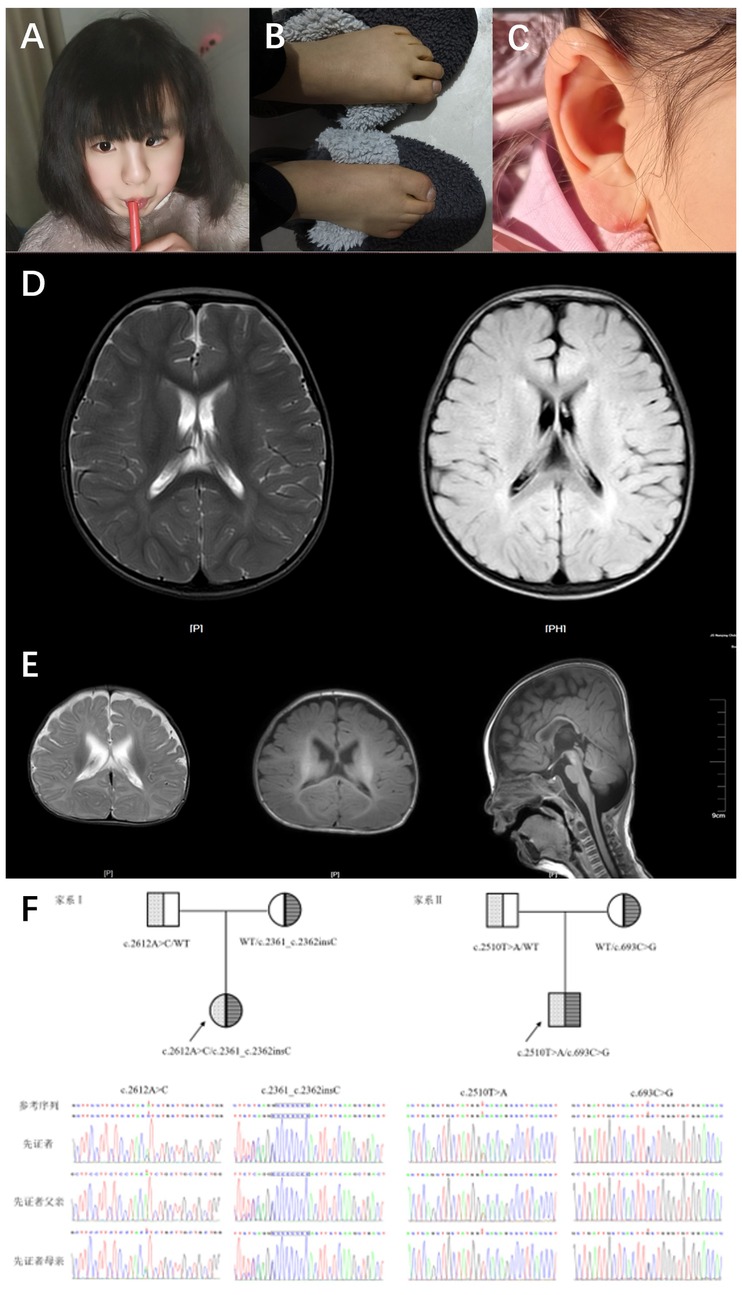

Patient 1 was a 5-year-and-2-month-old girl who presented to the Rehabilitation Department of Nanjing Children's Hospital in December 2019 due to “delayed language development.” During her initial consultation, she demonstrated the ability to call out names and produced approximately 10 words or syllables, including “ba,” “ma,” and “nai,” but was unable to form short sentences. She did not experience seizures but exhibited hyperactivity, poor concentration, and no signs of motor regression or stereotypic behaviors. The patient began walking independently at 24 months. The physical examination revealed decreased sensitivity in visual, auditory, and facial reflexes, along with ear deformities (Figure 1A), strong and bulky limbs, yellow skin color, and excessive skin keratinization (Figure 1B). Although the patient displayed a poor communicative attitude and did not cooperate during the examination, she could produce sounds spontaneously. She recognized facial features but could not indicate object size or quantity and could not distinguish colors; nevertheless, she could follow simple instructions. A brain MRI revealed widened extra-axial spaces. The parents reported that the patient's alkaline phosphatase levels fluctuated between 600 and 900 U/L during a follow-up phone call. To date, the patient has not received comprehensive rehabilitation treatment. Currently, she exhibits strabismus (Figure 1C) and has shown some improvement in both motor and cognitive abilities. She can ascend and descend stairs but cannot hop on one foot. There is increased muscle tone in both lower limbs, and she can now recognize colors and distinguish object sizes. She is able to follow simple instructions; however, there has been no significant improvement in her language skills. Her lexicon has expanded to approximately 30 words, including single words such as “ba”, “ma,” “nai,” “la,” and “yu,” but she remains unable to form short sentences. The patient is a full-term infant, classified as G1P1, delivered via Cesarean section with a birth weight of 3.5 kg. The pregnancy was uncomplicated, and the infant had APGAR scores of 10 at 1 and 5 min, with no history of asphyxia or hypoxia at birth. The infant experienced mild pathological jaundice with concurrent infection and has a history of recurrent otitis media. The parents are not closely related and deny any family history of hereditary neurological disorders.

Figure 1. Typical features and brain MRI in 2 cases with HPIDS2. (A) Patient 1 (9 years 3 months) facial photo, showing left eye esotropia. (B) Patient 1 (9 years 3 months) foot and toe photo, showing thickened toes, yellow skin, and excessive skin keratinization. (C) Patient 1 (9 years 3 months) ear photo, showing ear malformation. (D) Patient 1's brain MRI shows the following findings: widened extra-axial spaces. (E) Patient 2's brain MRI shows the following findings: 1. Bilateral enlargement of the lateral ventricles, with widened extra-axial spaces in the temporal and frontal regions on both sides. 2. Slight delay in myelination. (F) Sanger sequencing chromatograms of PIGO gene mutations in two HPIDS2 patients from the family. The mutated bases are indicated by red arrows and blue boxes.

Patient 2 was a 4-month-and-28-days-old boy who presented to the Rehabilitation Department of Nanjing Children's Hospital in August 2022 for “delayed motor and cognitive development.” Upon admission, he could not lift his head steadily, coughed during feeding, and exhibited upward eye deviation and limited spontaneous movement. EEG results were normal. The patient weighed 7 kg, had a triangular face with a high nasal bridge, and showed unstable muscle tone with involuntary movements. He could not bring both hands to the midline or grasp objects voluntarily. When pulled to a sitting position, he tilted his head back. In the prone position, he could not lift his head to 90 degrees or provide active elbow support, and when supported to sit, he leaned forward. Assisted standing revealed that his lower limbs could not bear weight. He could track objects to 90 degrees, responded to sounds, and exhibited nasal speech when crying. A prior MRI showed no significant abnormalities, and alkaline phosphatase levels were within normal limits. The patient's rehabilitation outcomes have been suboptimal; The patient has received intermittent comprehensive rehabilitation therapy to date, demonstrating improvement in motor skills and cognitive function compared to previous assessments. However, development remains delayed compared to age-matched peers. Currently, the patient is ambulatory but exhibits an abnormal gait characterized by pes valgus and external rotation of the feet. Communication skills are significantly impaired, with poor engagement and uncooperative responses during assessment. The patient is unable to follow simple instructions, differentiate sizes or quantities, or identify colors. Eye contact is fleeting, and vocalizations primarily consist of single syllables with an absence of words or phrases. Restricted interests are evident, manifested by repetitive lining up of toy cars. Cranial MRI reveals: 1. Bilateral lateral ventriculomegaly with widening of the extra-axial spaces in the temporal poles and frontal vertex. 2. Slightly delayed myelination. Elevated serum alkaline phosphatase (523 U/L) is also noted. The patient is classified as G2P2 (the first child is a healthy 7-year-old girl), born full-term via cesarean section with a birth weight of 3.7 kg, and the infant had APGAR scores of 10 at 1 and 5 min, with no history of asphyxia or hypoxia at birth. Mild jaundice was noted at birth. The mother experienced anemia during pregnancy, and parents are not closely related, denying any family history of hereditary neurological disorders.

Whole exome sequencing (WES) results revealed that Patient 1 and Patient 2 carried compound heterozygous variations in the PIGO gene: c.2612A>C (p.His871Pro)/c.2361dup (p.Thr788Hisfs*5) and c.2510T>A (p.Val837Asp)/c.693C>G (p.Phe231Leu), respectively (Figure 1F). According to the ACMG variant classification criteria, these variations were classified as variants of uncertain significance and pathogenic variants (Table 1). Multiple protein-damaging prediction software indicated deleterious effects, while tertiary structure simulations demonstrated alterations in hydrogen bonds and interacting forces, potentially impacting the correct folding and functional conformation of the active protein (Figure 2A). The phenotypes and genotypes of the proband and their parents exhibited co-segregation, consistent with the clinical phenotype and the autosomal recessive (AR) compound heterozygous inheritance mechanism. Therefore, the aforementioned genetic variants are believed to contribute to the pathogenesis of the disease.